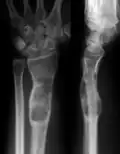

X-ray image showing enchondromas localized in the lower part of the radius of a 7-year-old girl with Ollier disease.

Abnormal bone growth such as shortening or thickening and deformity may be observed in patients of Ollier disease. These bone lesions are visible at birth using radiography but are usually not screened or examined for until clinical manifestations present during early childhood. However, some patients may exhibit no signs of any symptoms.[1] One study found thirteen to be the mean age of diagnosis in patients with Ollier disease. In an X-ray, there would normally be the presence of several homogeneous lesions of an oval or elongated shape with bone edges that are slightly thickened.[3] With age, these lesions may calcify and appear as diffusely minute spots or stippled. Fan-like septations or streaks would be indicative of the presence of several enchondromas. Early detection and consistent and repeated monitoring is important in order to prevent and treat any potential bone neoplasms.